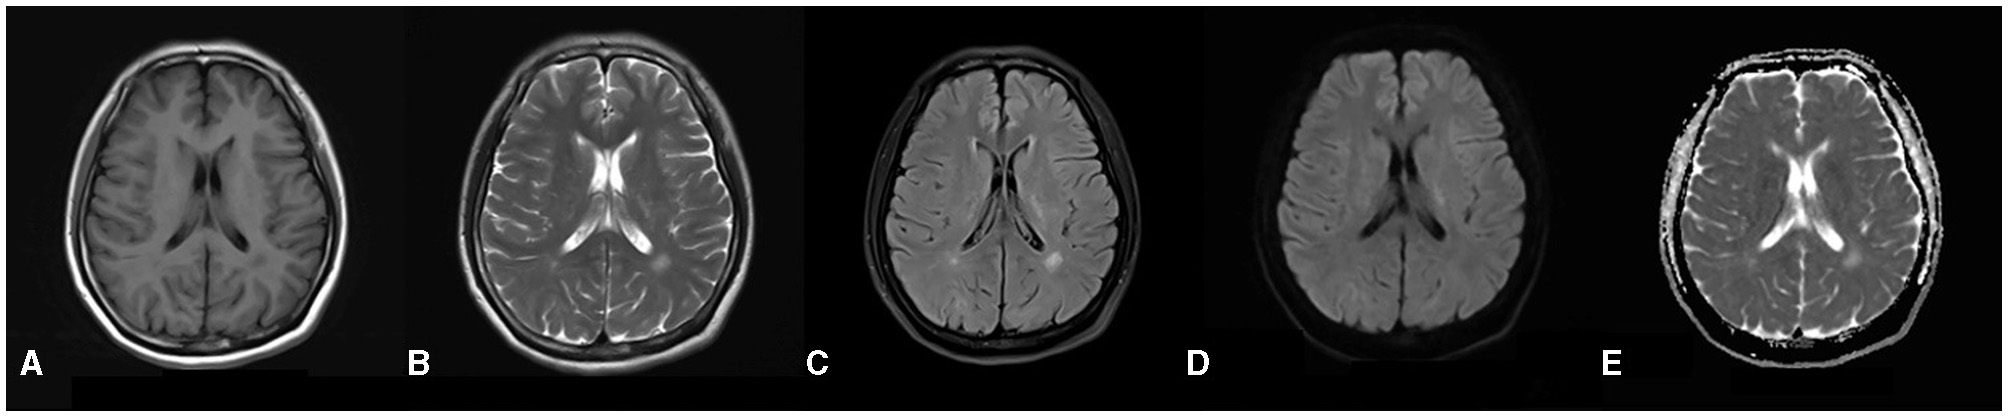

The total score of the scale for the assessment and rating of ataxia was 24, and the single-item scores were gait (score 5), stance (4), sitting (2), speech (2), finger chase (2), nose–finger test (2), fast alternating hand movement (3), and heel–shin slide (4). The patient's Mini-Mental State Examination score was within the normal range, and she failed to complete the Montreal Cognitive Scale due to tremors of the hands and head. The results for tumor markers, ceruloplasmin, immune-related autoantibodies such as the five items of thyroid function (thyroid stimulating hormone, free T3, free T4, thyroglobulin antibody and thyroid peroxidase antibody), three items of rheumatism (rheumatoid factors, anti-streptolysin O and high-sensitivity C-reactive protein), five items of immunity (immunoglobulin G, immunoglobulin A, immunoglobulin M, complement C3 and complement C4), antinuclear antibody, anticardiolipin antibody, and screening and confirmation of anti-neutrophil cytoplasmic antibody were not significantly abnormal. Lumbar puncture results for the patient showed no abnormalities. Brain MRI revealed speckled and small patchy abnormal signals bilaterally in the corona radiata, the paraventricular and frontal lobes, and the left temporal lobe. The lesions appeared hypointense on T1 images and hyperintense on T2 and FLAIR images. There were no obvious abnormal signals on diffusion-weighted images (DWI) and apparent diffusion coefficient maps (Figures 1A–E). The radiological diagnosis was multiple white matter demyelinating lesions. Color Doppler ultrasonography of the gynecological, abdominal, cardiac, carotid, and intracranial arteries revealed no obvious abnormalities.

Figure 1

(A–E) Brain MRI reveals a distribution of abnormal signals localized around the ventricles, as well as within the frontal and temporal lobes. In the T1-weighted images, there is a depiction of slightly hypo-intense signals (A), while the T2-weighted images illustrate hyper-intense signals (B). The dark-field images similarly exhibit hyper-intense signals (C). Furthermore, both diffusion-weighted images and apparent diffusion coefficient (5) images do not indicate any restrictions in diffusion (D, E).